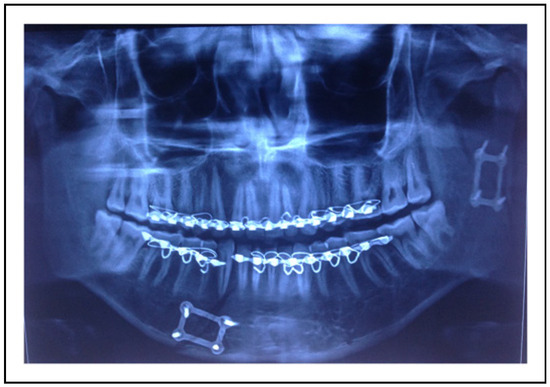

| Sr No. | Author, Publication Year & Country | Age Range | Male/Female | Two Miniplates Group | 3 D Plate Group | Parameters Assessed | Type of 3D Plate |

| 1. | Adhikari et al (2021) [14] India | 18+ years | 46/6 | 26 | 26 | 1. Intra-operative time taken for fixation 2. Ease of plate adaptation 3. Postoperative status of occlusion 4. Radiographic plate fracture 5. Maximum mouth opening 6. Protrusive, ipsilateral, and contralateral movements 7. Facial nerve status 8. Complications like development of a temporomandibular disorder, sialocele, infection, or hypertrophic scar. | Trapezoidal plate |

| 2. | Ahuja et al (2018) [15] India | 18 to 60 years | 17/3 | 10 | 10 | 1. Intra-operative time taken for fixation 2. Ease of plate adaptation 3. Postoperative status of occlusion 4. Need for intermaxillary Fixation 5. Maximum mouth opening 6. Lateral excursive and protrusive movements | Delta plate |

| 3. | Ganguly et al (2021) [16] India | 16+ years | 18/2 | 10 | 10 | 1. Complications like pain, wound dehiscence, infection 2. Mouth opening and lateral deviation while mouth opening 3. Biting efficiency 4. Need for postoperative intermaxillary fixation 5. Radiographic assessment of fracture reduction 6. Bite force | Delta plate |

| 4. | Rai et al (2021) [17] India | 21 to 59 years | 43/15 | 35 | 23 | 1. Occlusal stability 2. Postoperative complications like plate fracture, non-union, plate or screw loosening, plate or screw infection leading to implant removal, wound dehiscence, salivary fistula, and facial nerve paralysis. 3. Radiographic evaluation of fracture reduction | Rectangular plate |

| 5. | Scott et al (2020) [18] India | 18 to 53 years | 40/4 | 22 | 22 | 1. Time taken for fixation 2. Maximum mouth opening 3. Occlusal stability 4. Radiographic evaluation of fracture reduction 5. Jaw movements | Trapezoidal plate |

| 6. | Sehgal et al (2014) [19] India | 18 to 60 years | 26/4 | 15 | 15 | 1. Intraoperative assessment of reduction of fracture 2. Stability of occlusion 3. Need for intermaxillary fixation 4. Post-operative complications like tissue dehiscence and infection. 5. Bone Union 6. Plate Fracture | Rectangular plate |

| 7. | Sukegawa et al (2019) [20] Japan | Not reported | 16/10 | 14 | 12 | 1. Complications like postoperative infection, facial nerve paralysis, nonunion, malunion, and occlusal insufficiency, foreign body sensation by an osteosynthesis plate, and plate removal 2. Postoperative stability and occlusion | MatrixMANDIBLE subcondylar plate |